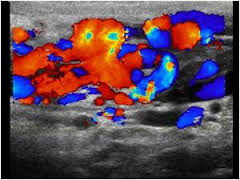

vascular

Varicocele